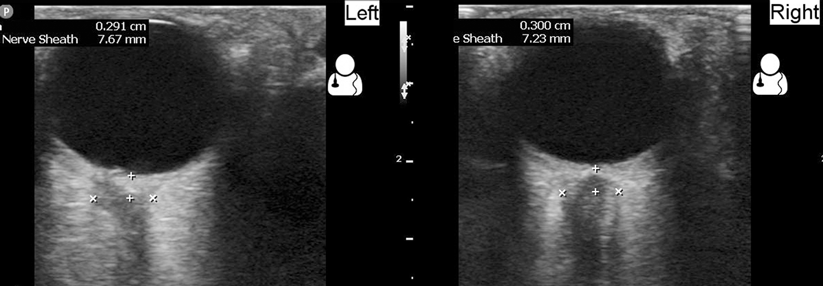

Die idiopathische intrakranielle Hypertension ist eng mit einer Adipositas assoziiert. Eine Gewichtsabnahme – in Zukunft möglicherweise unterstützt durch GLP1-Rezeptoragonisten – ist die effektivste Therapieoption.